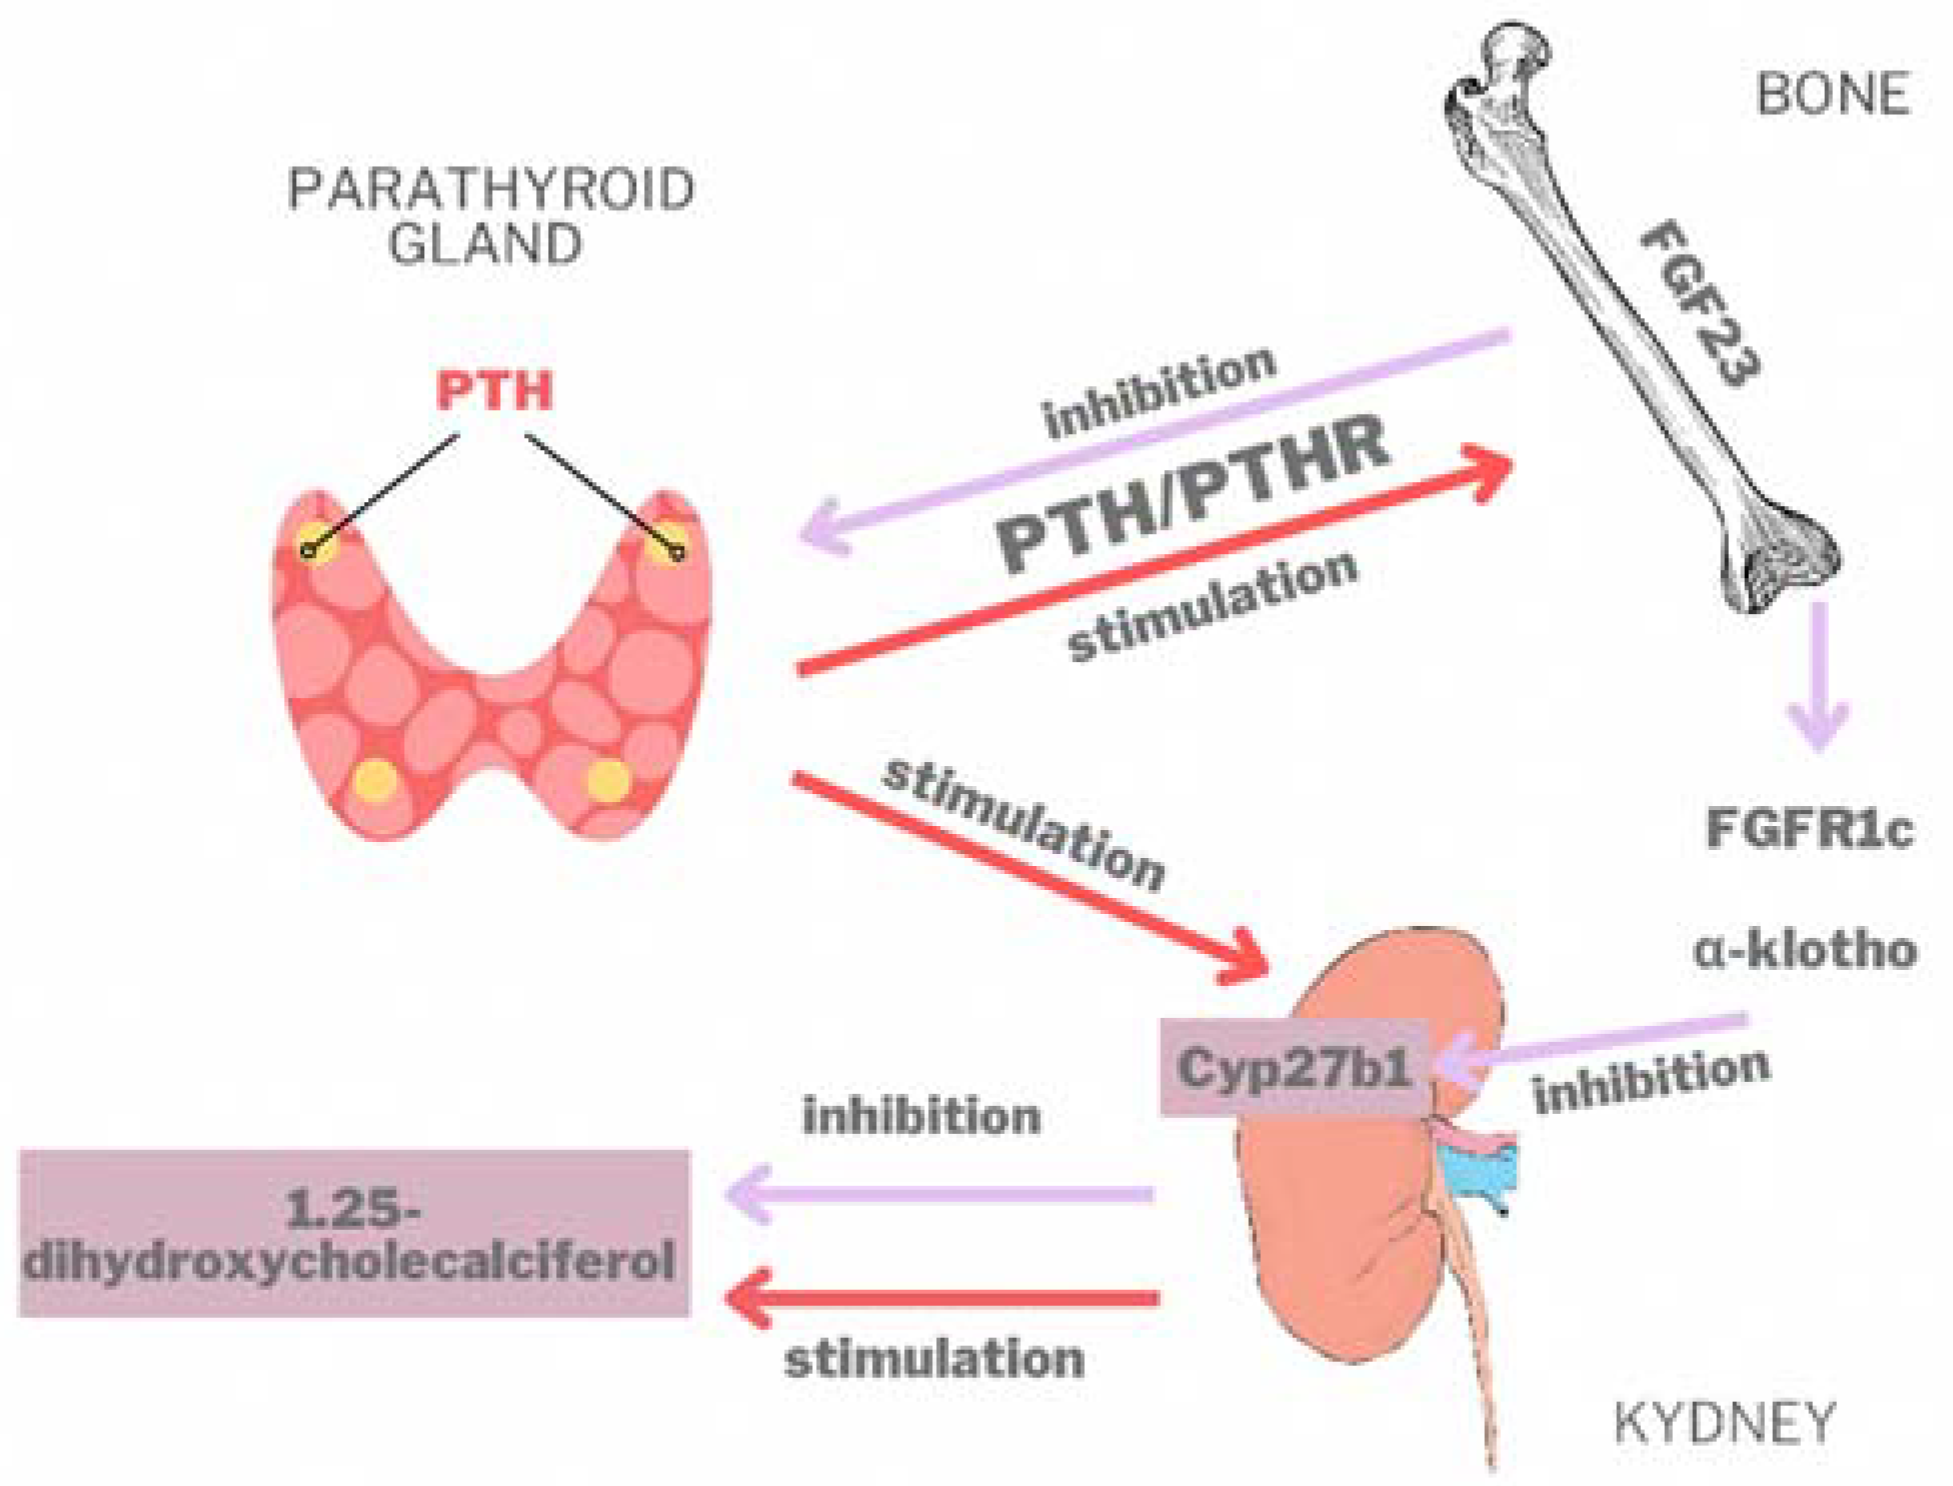

4. Discussion

4.3. Paraclinical Aspects